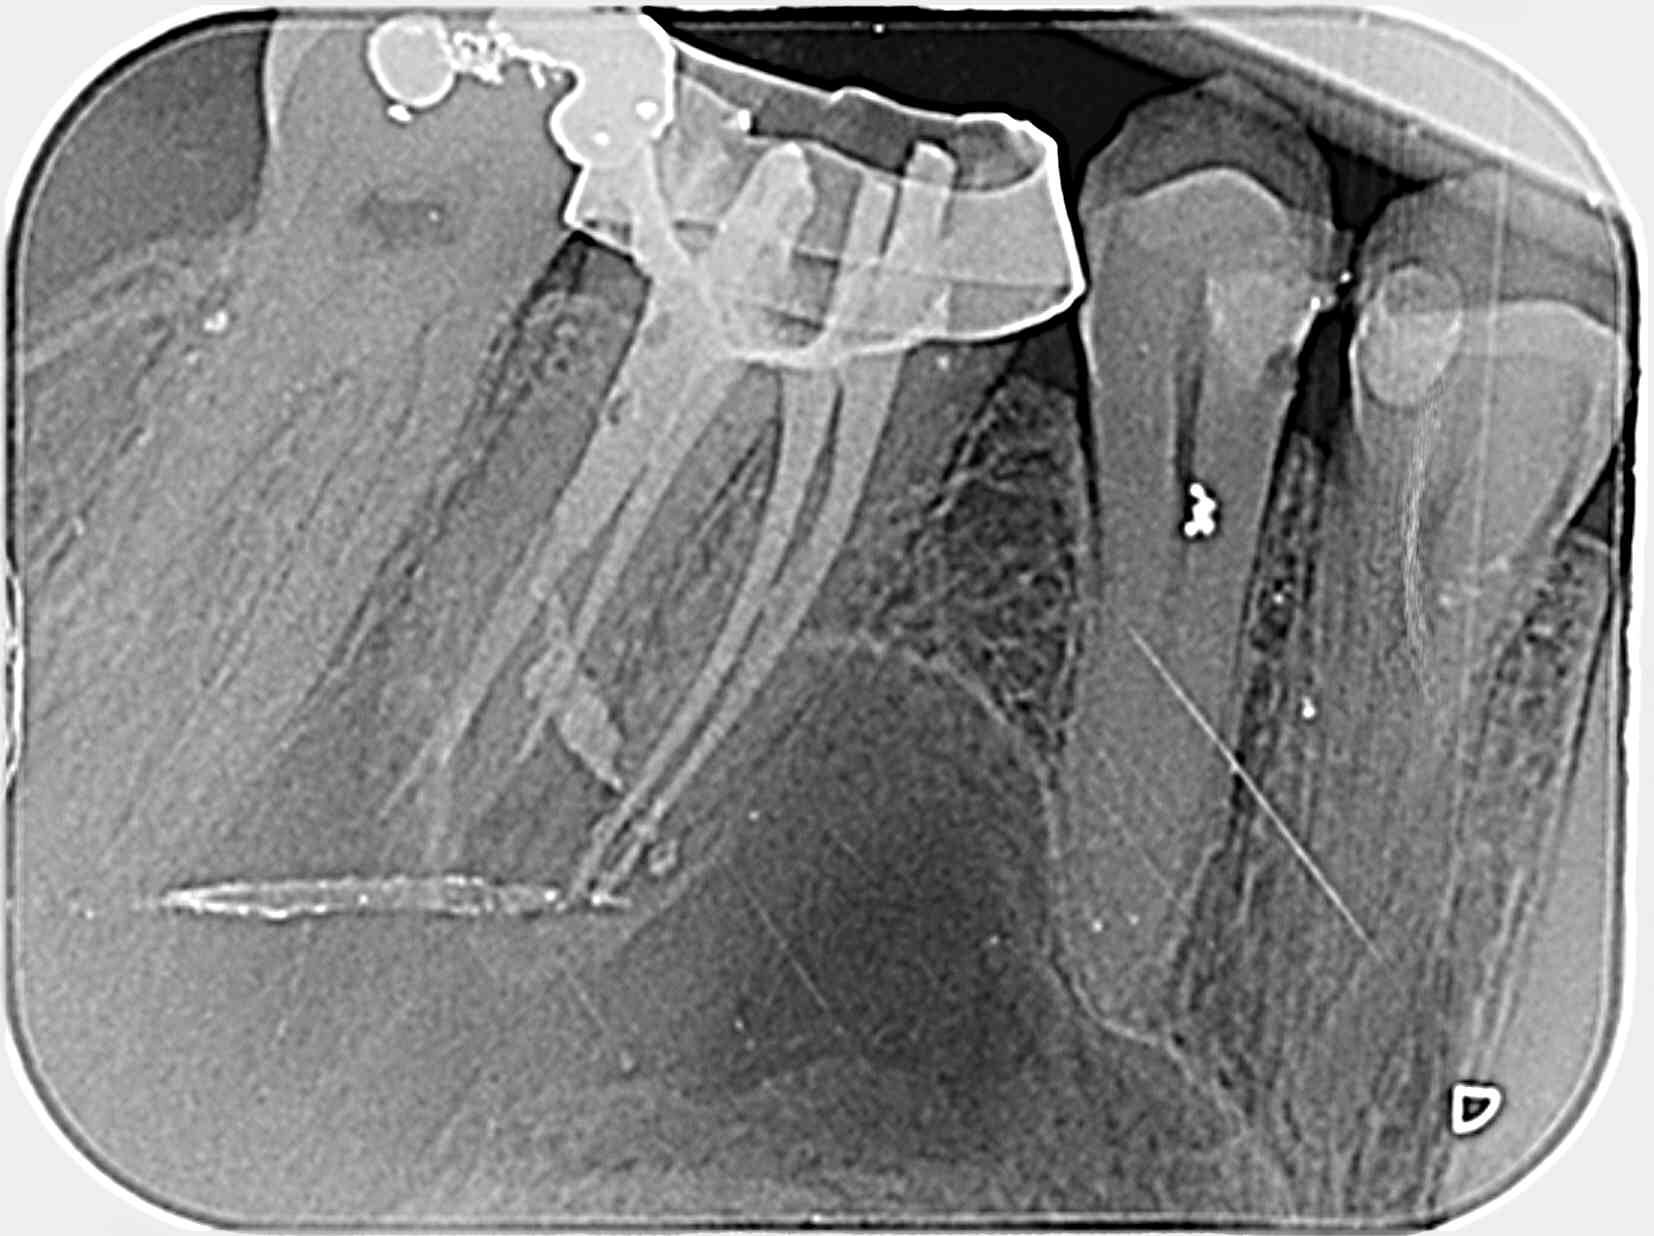

Retraitement de 17 et 16 en 2 temps.

La 17 retraitée en janvier présentait un canal MV en lame de couteau, comme décrit plus haut. La radio n'était pas si affolante que ça quant à la qualité du précédent traitement, et pourtant j'ai sorti des kilos de merde du canal.

La 16 présentait un MV2 distinct, non traité, mais qui ne semblait pas "visuellement" infecté.

La patiente a fait un covid il y a 10 jours, et me décrit au téléphone une récidive de l'infection de 17.

Elle se sent gonflée dans la zone, peut-être faudra-t-il extraire.

Des fois, même quand le traitement semble propre, ça veut pas.

Echec de cicatrisation sur une endo "semblant" parfaitement réalisée.